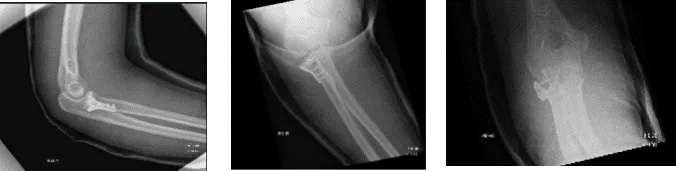

Figure 1. AP Oblique and Flexion Lateral Projection of Right Elbow

Hemarthrosis and a comminuted, affected, acute radial head fracture is present. The plantar-medial portion of the proximal shaft of the right ulna is home to a fracture fragment that has been severely misaligned. Though no donor defect is visible, this could be a fragment of the radial head that has been significantly displaced. A second fracture site is also a possibility.